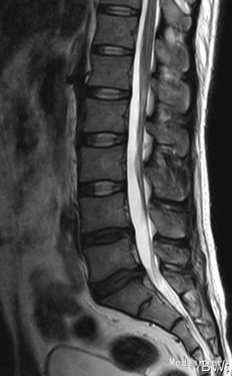

35岁 男性 主诉:反复右下肢放射性疼痛麻木8个月,加重3天

生命体征平稳,痛苦表情, 专科查体: 右下肢强迫性屈髋屈膝位; L5/S1棘突间及右侧椎旁压痛,并向右下肢放射; 右小腿后侧及足背外侧皮肤感觉减弱; 右足拇跖屈肌力3级; 右侧直腿抬高试验5°(+), 右侧跟腱反射消失。 入院三大常规,生化指标等均正常范围

诊断:腰椎间盘突出症 (腰5/骶1髓核游离型) VAS评分:9分 ODI评分:96% 疼痛剧烈,右下肢难以伸直,坐卧不宁;给予常规脱水,激素,止痛等治疗无效;不同意手术,反复要求保守治疗。 保守治疗3天,患者疼痛仍无明显缓解,同意行手术治疗 手术方案:椎板间隙入路PELD 术后予以止痛,脱水,小剂量激素等治疗, 术后第二天:右下肢麻木疼痛明显缓解。查体:右小腿后侧及足背外侧皮肤触觉恢复;右足拇跖屈肌力4+级;右侧直腿抬高试验(-);右侧跟腱反射仍减弱。 术后第5天:出现右小腿及足底针刺样疼痛症状加重,麻木感,伴有右下肢间歇性抽搐,次数较频繁,以夜间为甚。查体:腰椎活动无明显受限,右小腿后面及右足背外侧触痛明显;双下肢屈伸肌力、肌张力基本正常;右侧直腿抬高试验(-),右侧跟腱反射仍减弱。 予以加大NSAID及地米治疗,效果不明显,夜间疼痛难以入睡。复查腰椎MRI,未见髓核再脱出,减压彻底 诊断:考虑右侧骶1神经根神经病理性疼痛 治疗: 普瑞巴林 75mg Bid;神经妥乐平 2# Bid; 阿米替林 25mg Bid 外加神经营养治疗 治疗1周后,症状明显缓解